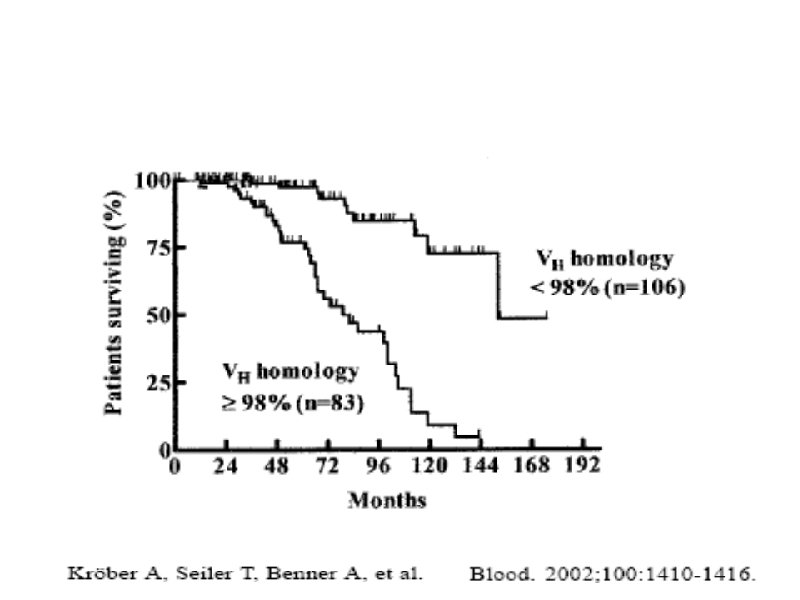

Время удвоения лимфоцитов менее 6 месяцев Время удвоения лимфоцитов более 6 месяцев Стадия на момент диагноза III – IV / C (Rai / Binnet) Возраст менее 65 лет I – II / A Возраст более 65 лет ZAP-70 < 20% Соматическая мутация (-) Соматическая мутация (+) 17 p делеция (p 53 мутация), 13 q делеция 11 q делеция, 12 q трисомия CD 38 (+) CD 38 (-)